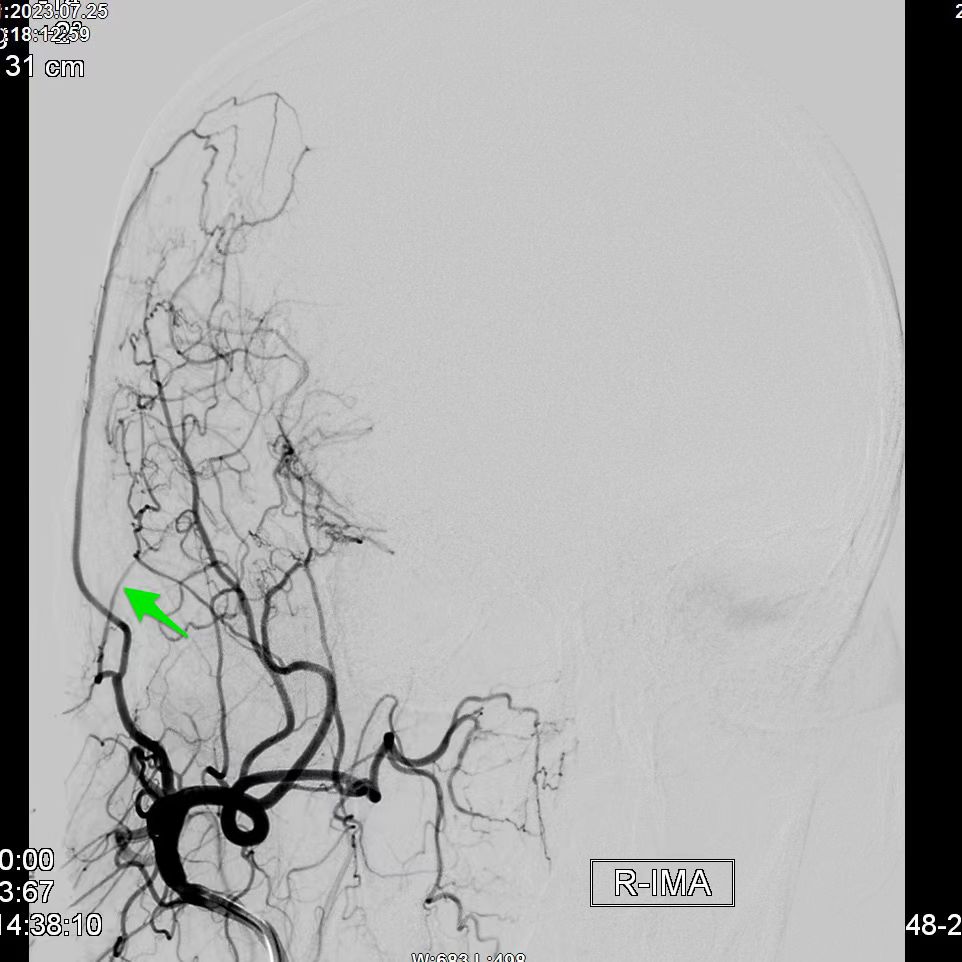

昆明三博2023:颞浅动脉一大脑中动脉M3吻合术